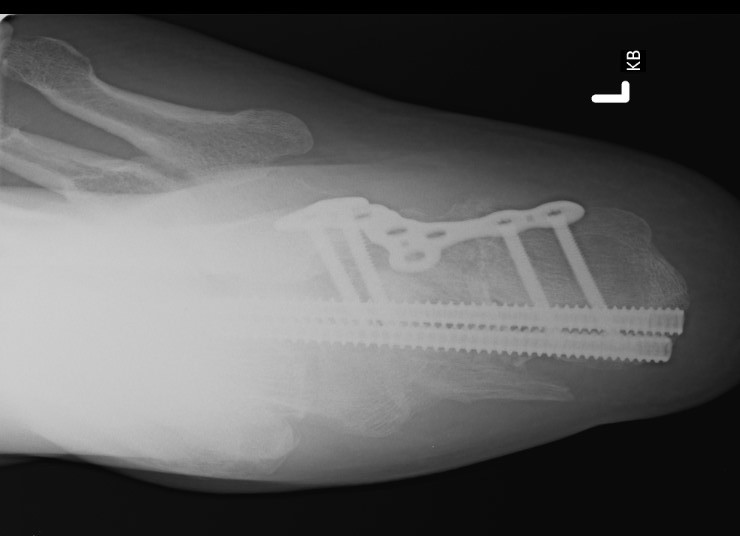

Minimally invasive surgery via sinus tarsi approach

Arthrex MIS calcaneal plating system

Acumed MIS calcaneal plating system

Technique

AO surgery sinus tarsi approach

AO surgery MIS calcaneal ORIF via sinus tarsi

MIS sinus tarsi technique article

Vumedi MIS calcaneum fracture via sinus tarsi

Vumedi MIS calcaneum fracture via sinus tarsi 2

Sinus tarsi approach

Use lateral plate with minimally invasive techniques